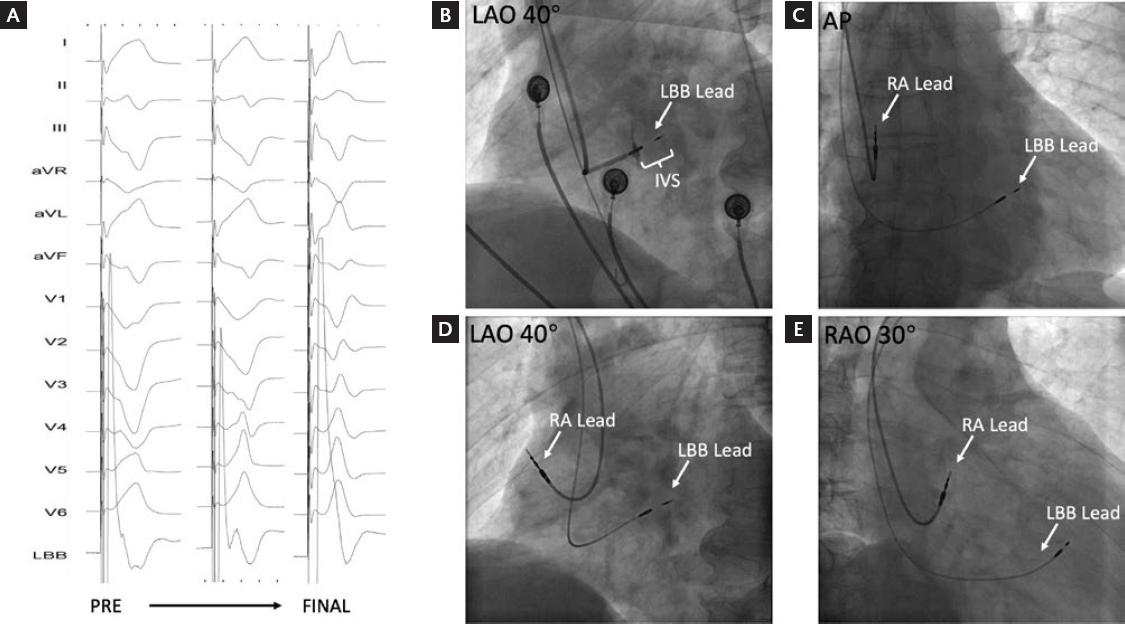

In total, 138 patients who underwent attempted LBBAP for symptomatic bradycardia were enrolled in this study. Finally, LBBAP was successfully achieved in 126 patients; in the remaining 12 patients, it failed and left ventricular septum pacing was chosen. Clinical characteristics of patients with LBBAP are summarized in table 1. The indications of pacemaker implantation were sinus node dysfunction in 70 patients (56%), atrioventricular block in 48 patients (38.4%), and atrial fibrillation with long RR interval in 7 patients (5.6%). Figure 1 shows the position of 3830 leads in the interventricular septum in successful LBBAP by X-ray and echocardiogram. Figure 2 shows the developing process of pacing ECG during LBBAP and the fluoroscopic images of sheath angiography and final stage.

Figure 2 The developing process of pacing electrocardiogram and fluoroscopic image of LBBAP. A, the developing process of pacing electrocardiogram (3.5 V at 0.5 ms) during LBBAP from pre-operative to final. B, the angiography image shows the position of 3830 lead stuck in the interventricular septum. C-E, final fluoroscopic image in three projections (AP, LAO40°, and RAO30°) of LBBAP. PRE: pre-operative; LBB: left bundle branch; RA: right atrium; IVS: interventricular septum.